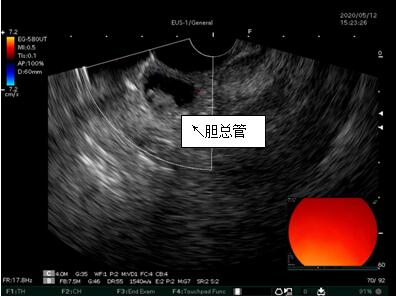

69歲王姓患者,因“發(fā)現(xiàn)無痛性黃疸1月”入院,根據(jù)患者病史,患者診斷傾向于壺腹部腫瘤所致梗阻性黃疸。予以完善腹部CT及上腹部MRI加MRCP均顯示肝內(nèi)外膽管擴(kuò)張,未發(fā)現(xiàn)明顯膽管,胰腺及十二指腸乳頭部腫瘤,且患者CA199正常。以前醫(yī)院未引進(jìn)超聲內(nèi)鏡,這類患者到此就遇到診斷瓶頸。此患者經(jīng)過消化內(nèi)科張丹霞副主任醫(yī)師完善超聲內(nèi)鏡檢查后,可以清楚顯示膽總管下段壁內(nèi)軟組織占位。患者通過超聲內(nèi)鏡檢查診斷明確,轉(zhuǎn)至肝膽外科行手術(shù)治療。

超聲胃鏡圖片

膽總管小腫瘤性病變CT及MRI檢查陽性率偏低,因其低代謝特征,PET-CT陽性率也偏低,超聲內(nèi)鏡對(duì)這類疾病的診斷陽性率是所有檢查中最高的,且可行穿刺活檢進(jìn)一步確診病灶性質(zhì)。

環(huán)掃超聲內(nèi)鏡主要用于胃腸道粘膜下腫物診斷,胃腸道腫瘤分期,發(fā)現(xiàn)早期胃癌等,扇掃超聲內(nèi)鏡主要用于診斷膽道及胰腺疾病,并且可行穿刺活檢取病理。